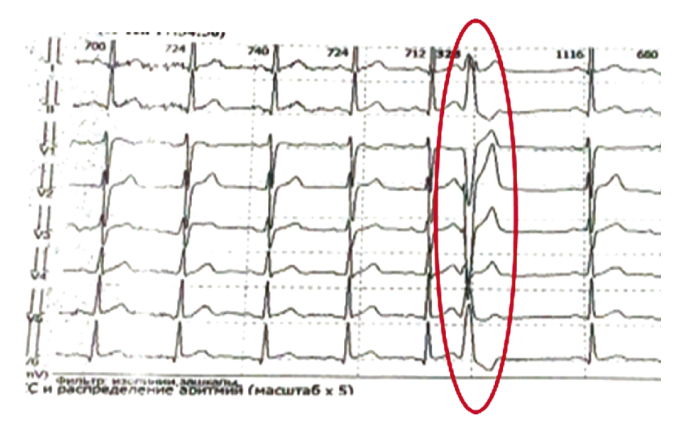

Рис. 4. Одиночные желудочковые экстрасистолы по типу блокады левой ножки пучка Гиса.

В результате дообследования изменена тактика лечения: пропафенон по 150 мг 3 раза/сут; магния оротат по 0,5 мг 3 раза/сут; этилметилгидроксипиридина сукцинат по 100 мг 3 раза/сут. Спустя месяц приёма назначенной терапии проведено повторное холтеровское мониторирование ЭКГ. Отмечалось уменьшение желудочковой и наджелудочковой эктопической активности в виде одиночных экстрасистол (рис. 4). По результатам повторного холтеровского мониторирования была снижена доза пропафенона до 150 мг 1 раз/сут.